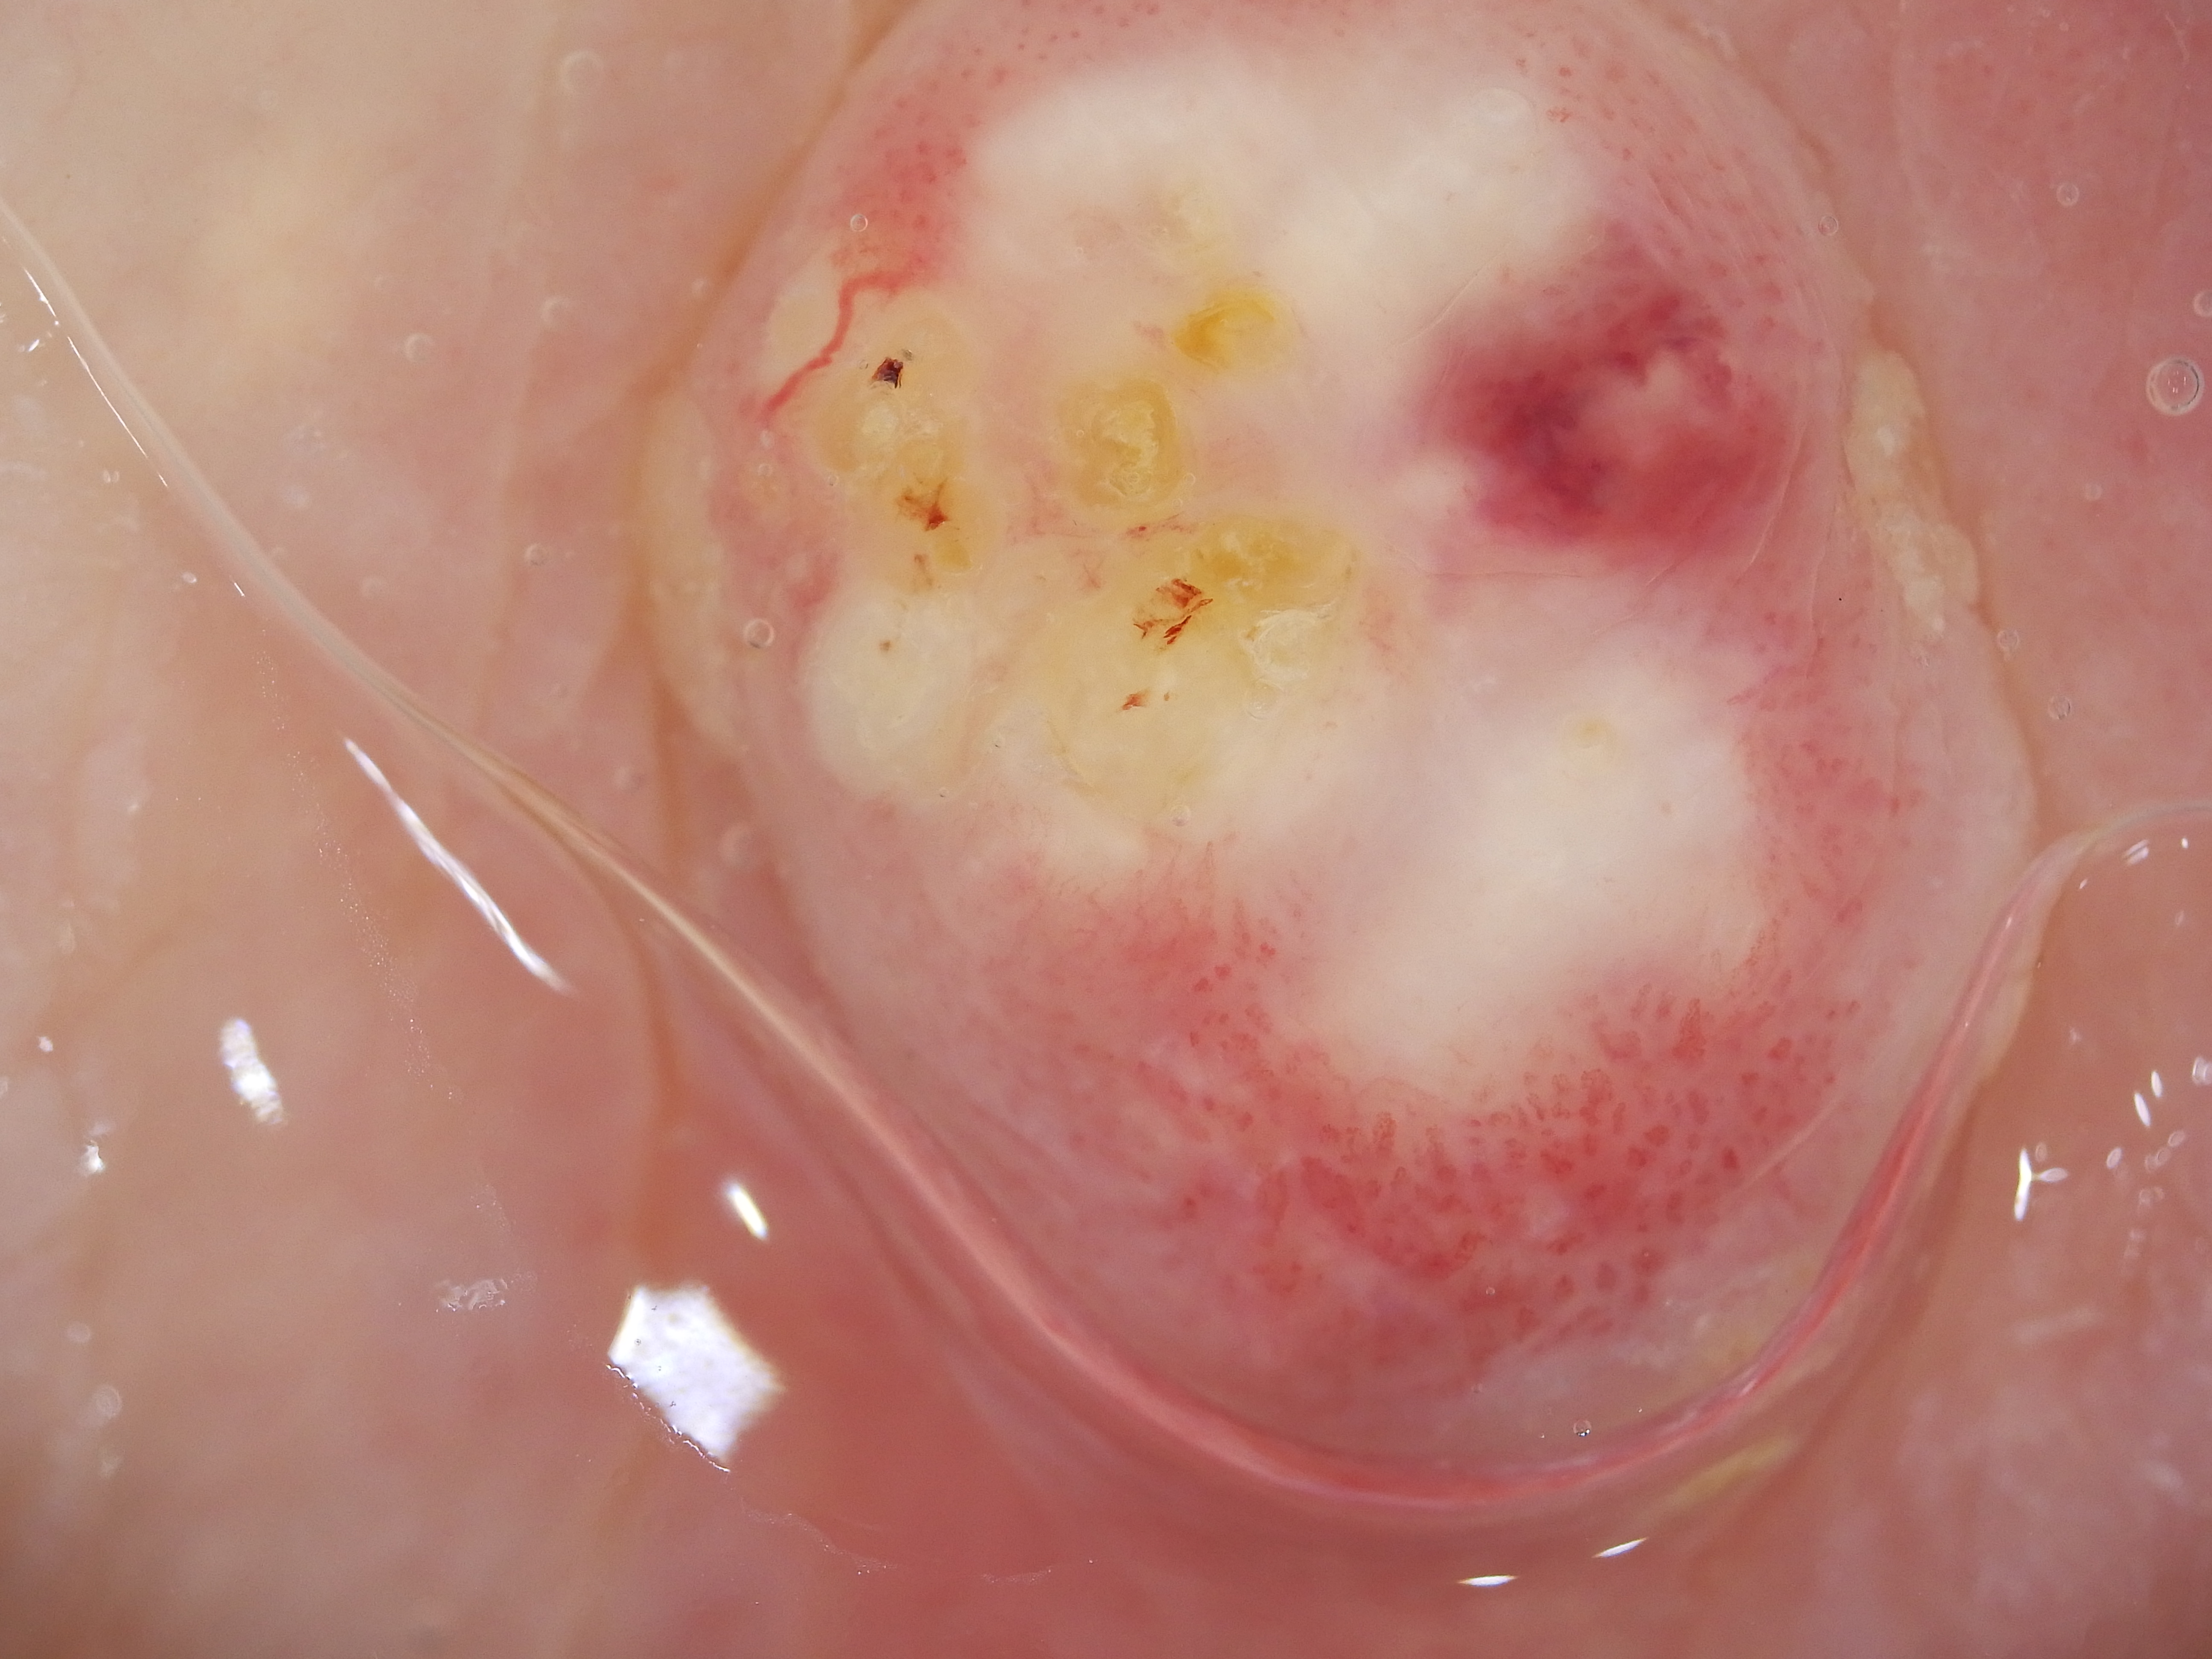

Site: Thigh

Diagnosis: Keratoacanthoma

Type: Dermlite Polarised

Description: Firm rapidly growing nodule on the thigh

This 99 years old lady developed this nodule on her thigh, It came up rapidly just after she ceaeased a Braf inhibitor drug for melanoma. It was reported as a keratoacanthoma. KAs and SCC like lesions are commonly seen in patients on Braf inhibitor drugs.

Dermatoscopy of SCCs and keratoacanthomas Dermatoscopy of solitary keratoacanthoma